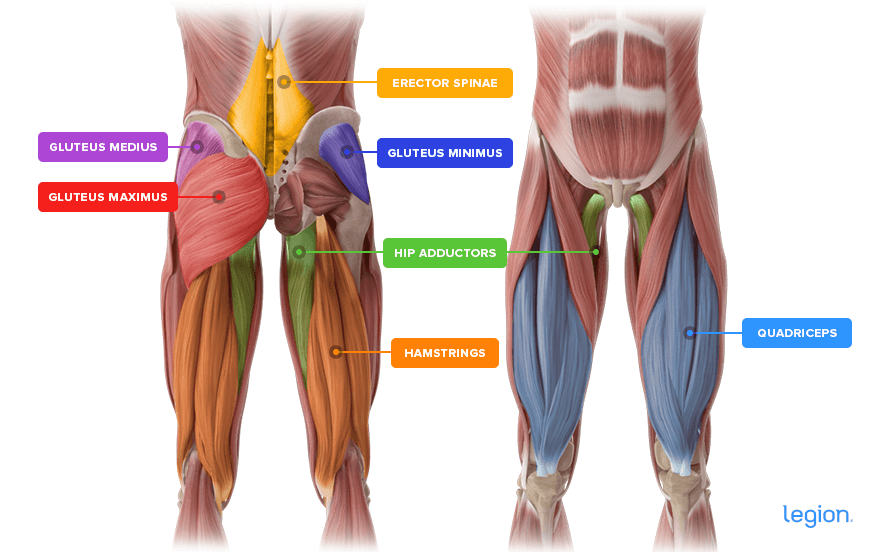

Анатомия и Функции Мышцы Adductor Magnus